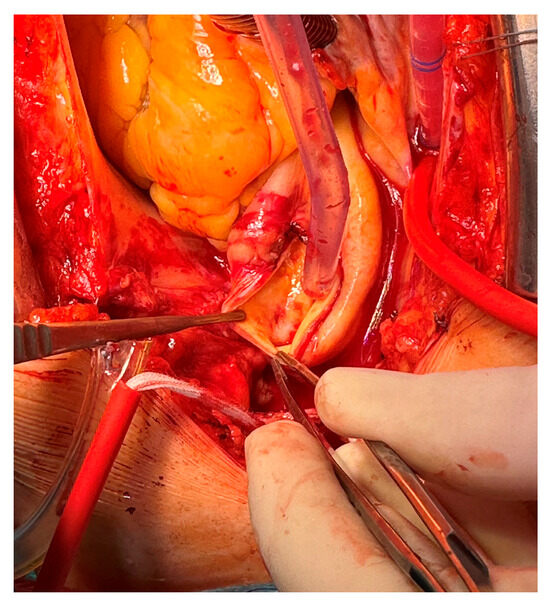

2. Case Presentation